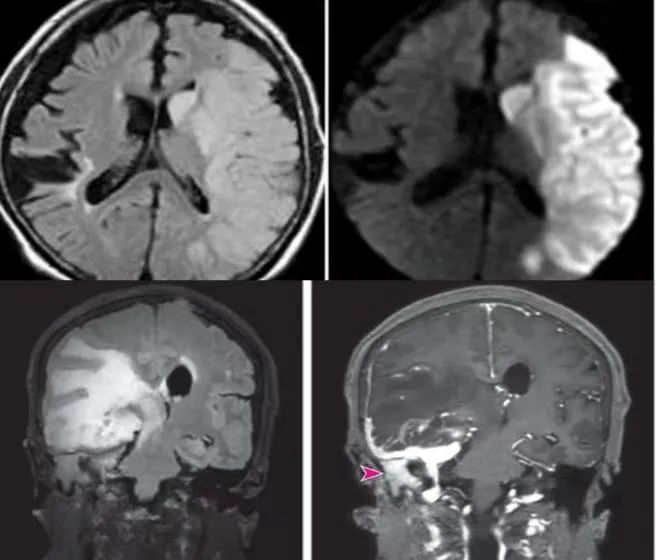

MRI检查:MRI即核磁共振成像,它利用磁场和射频脉冲使人体内的氢原子发生共振,从而生成图像。MRI检查对软组织具有很高的分辨率,常用于脑部、脊柱、关节等疾病的诊断。